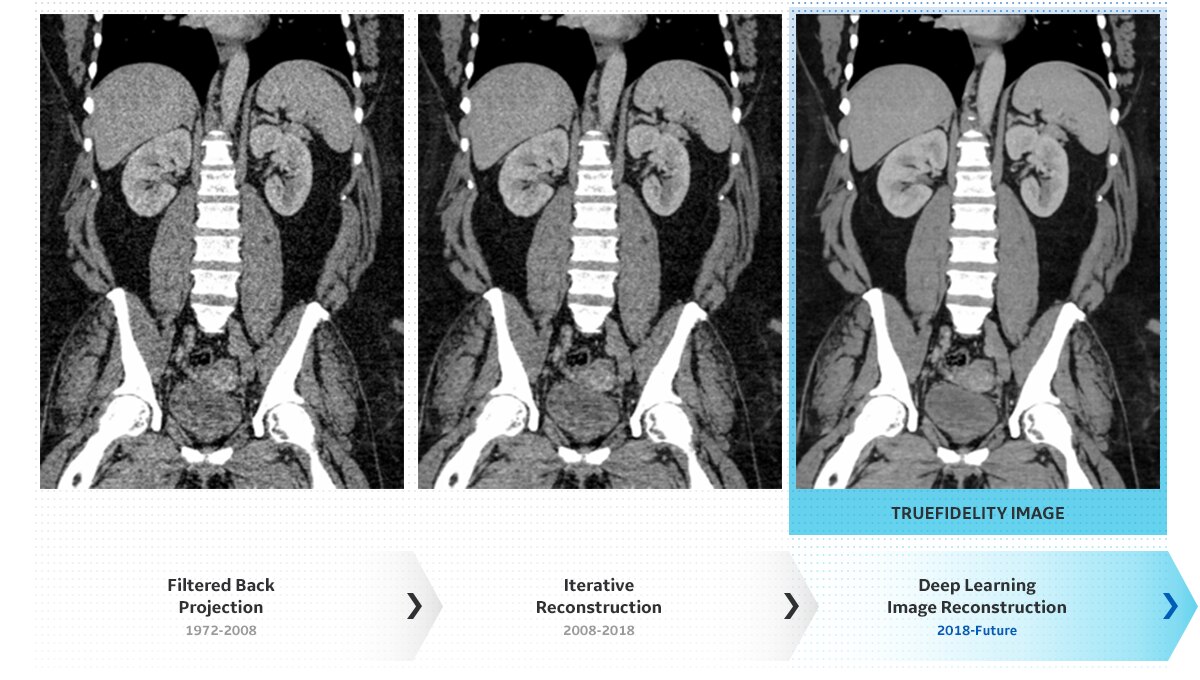

BMI 62患者のTrueFidelity画像

『True Fidelity 新時代の画像再構成法』ディープラーニングによる画像再構成に関するテクニカルホワイトペーパー(英語原本)では、フィルタ補正逆投影法と逐次近位再構成法が有する課題を踏まえ、ディープラーニングベースの画像再構成法についてファントム実験や症例集などのエビデンスも交えて詳細に解説しています。是非PDFファイルをダウンロードしてご覧ください。